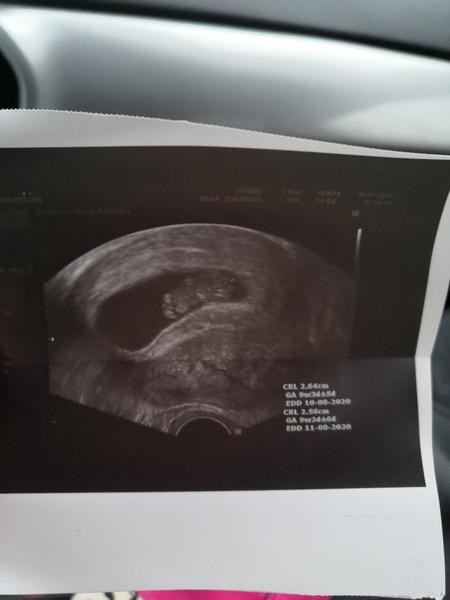

@fialka444 7+0

@fialka444 5+5